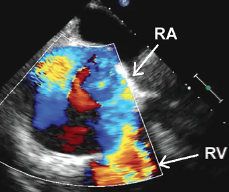

Ahmadreza Karimianpour, DO; Gary P. Miller, MD; Brian W. Zagol, MD

A 73-year-old woman with no known history of coronary artery disease presented to the emergency department with complaints of sudden-onset left-sided substernal chest pain characteristic of myocardial...

11/18/2015